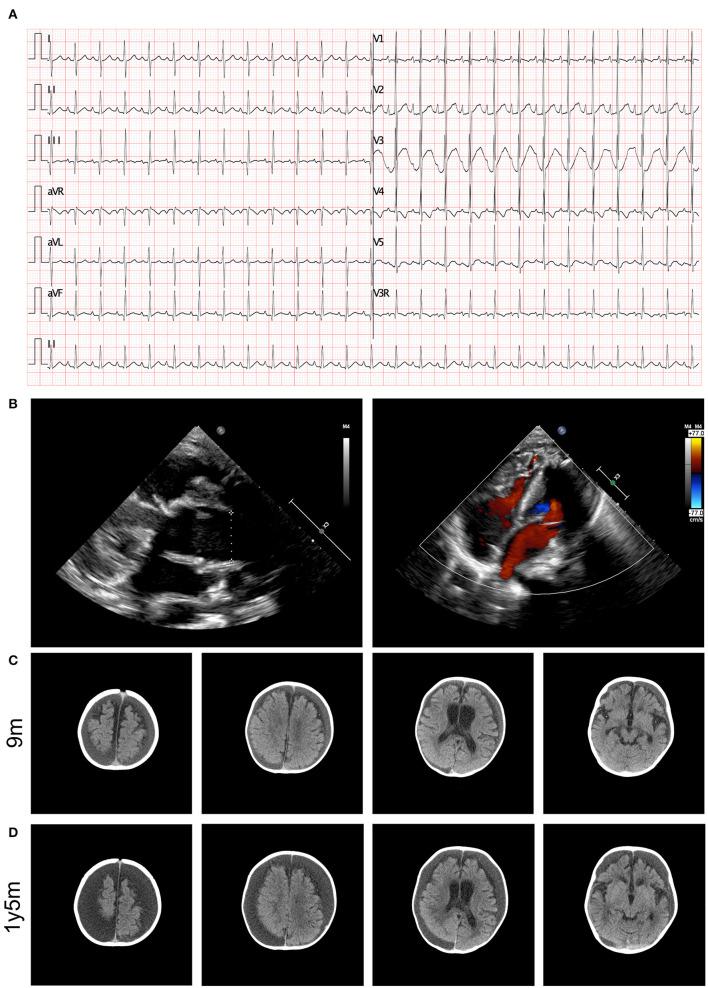

Exome sequencing and variant analysis of were performed to obtain genetic data, and clinical characteristics were determined. A complex and severe form of CHD, comprising a persistent truncus arteriosus type I, ventricular septal defect, right aortic arch, as well as critical neurodevelopmental delay and neurological dysfunction, was observed in a patient. This proband presented global muscle hypotonia and a significant delay in gross and fine motor development. Cranial computed tomography scanning showed the presence of bilateral apical, occipital, and temporal subdural effusions; slightly wider bilateral lateral ventricles and annular cisterns; and bilateral cerebral hemispheric parenchyma atrophy. Upon genetic analysis of the patient, a novel homozygous mutation was identified in the gene. The mutation, c.1336_1339DEL, was found to be homozygous and resulted in a frameshift mutation, causing a p.L447Vfs9 amino acid change. This mutation led to the deletion of a TCTC sequence from positions 1336 to 1339 in the gene, changing leucine to valine at amino acid 447 and introducing a stop codon after the ninth amino acid. This structural deletion in the protein resulted in the loss of gene function.

对患者进行外显子组测序和变异分析以获取基因数据,并确定临床特征。在一名患者中观察到一种复杂且严重的CHD形式,包括I型永存动脉干、室间隔缺损、右主动脉弓,以及严重的神经发育延迟和神经功能障碍。该先证者表现出全身肌张力减退以及粗大和精细运动发育明显延迟。头颅计算机断层扫描显示双侧顶部、枕部和颞部硬膜下积液;双侧侧脑室和环池稍宽;以及双侧大脑半球实质萎缩。对该患者进行基因分析时,在基因中鉴定出一个新的纯合突变。该突变c.1336_1339DEL被发现是纯合的,导致移码突变,引起p.L447Vfs9氨基酸变化。该突变导致基因中第1336至1339位的TCTC序列缺失,使第447位氨基酸的亮氨酸变为缬氨酸,并在第九个氨基酸后引入终止密码子。该蛋白中的这种结构缺失导致基因功能丧失。